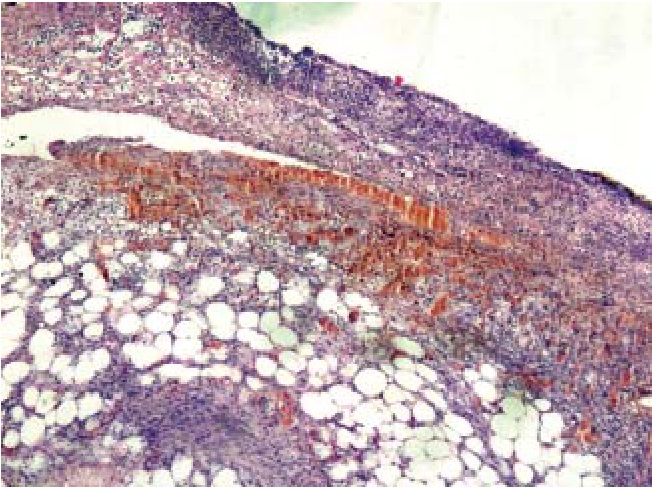

Наиболее характерным для острых перфоративных язв тонкой кишки было первичное повреждение слизистого слоя с развитием множественных некрозов эпителия (рис. 4, 8) на фоне массивной нейтрофильной инфильтрации (рис. 4–8) и значимых гемоциркуляторных расстройств в виде резкого полнокровия и тромбозов сосудов, а также геморрагического пропитывания как слизистого, так и подслизистого слоев (рис. 5, 7, 8), массивного разрастания в подслизистой основе грануляционной ткани (рис. 6) с исходом в фиброз и липоматоз (рис. 8).

Рис. 4. Край язвы слизистой тонкой кишки: некрозы слизистой оболочки, нейтрофильная инфильтрация подслизистой основы, грануляции. Окраска гематоксилин – эозином, ув. ×100